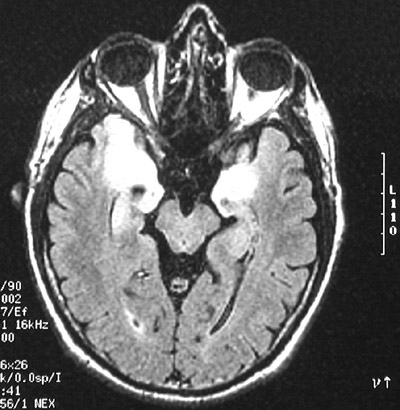

| This axial view of a FLAIR MRI scan reveals limbic encephalitis involving temporal lobes bilaterally. This inflammatory process is most likely to involve medial temporal lobe, amygdala, hypothalamus, and hippocampus. The marked brightness of the lesions is seen early in the course of this disease. |